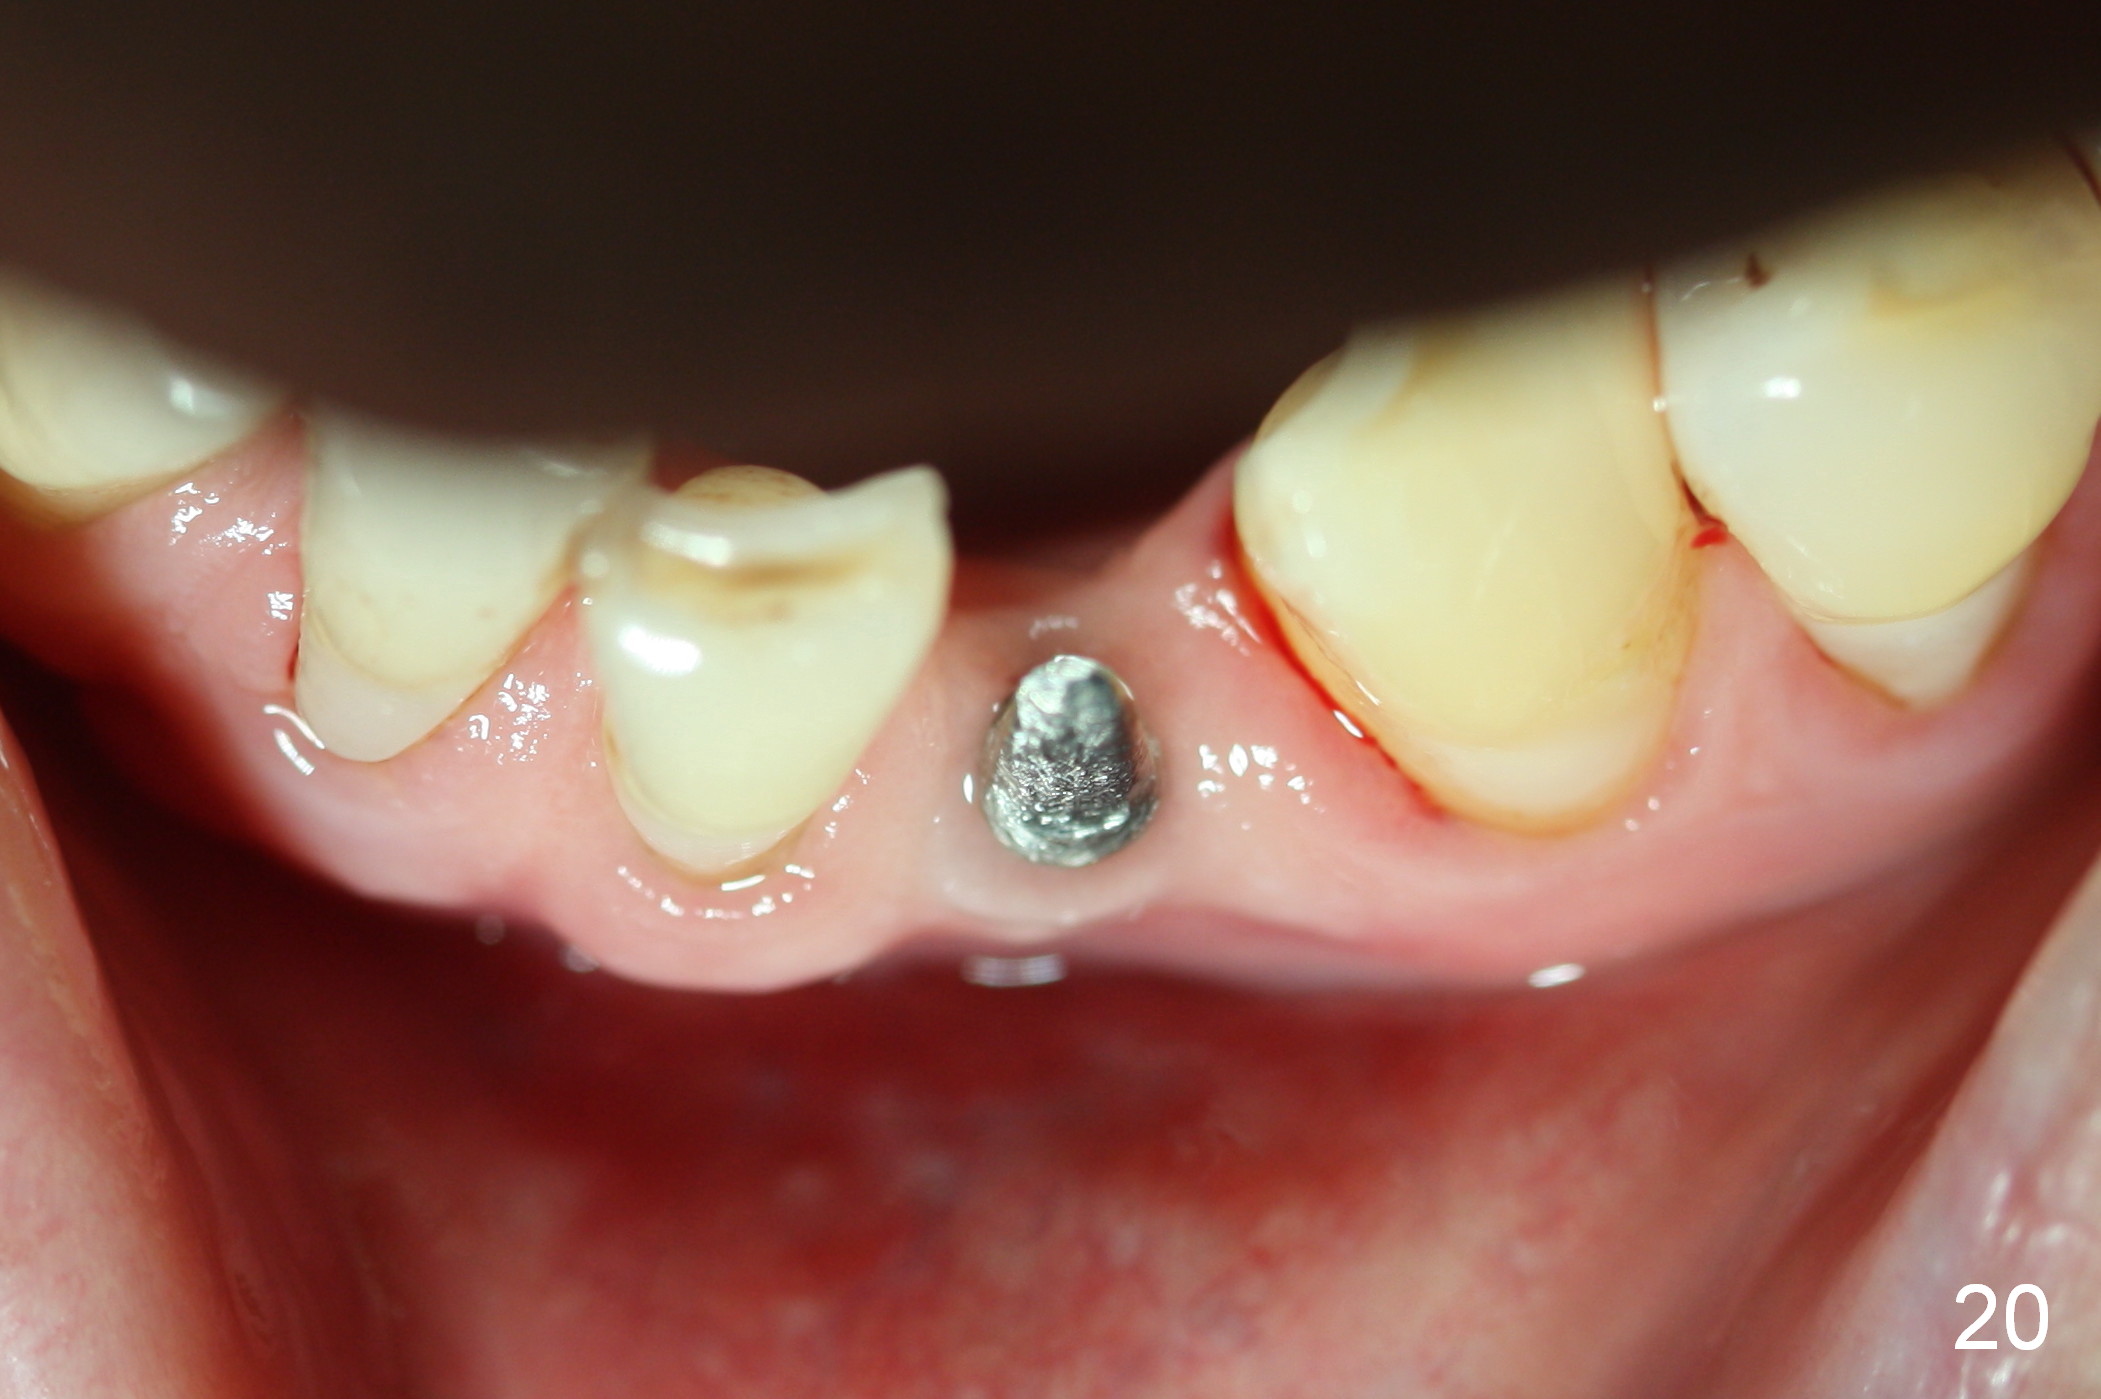

Five months postop, the peri-implant space reduces (Fig.18).  A keratinized band forms buccal to the implant (Fig.19 *).  The provisional dislodges probably due to the buccal placement (Fig.20).